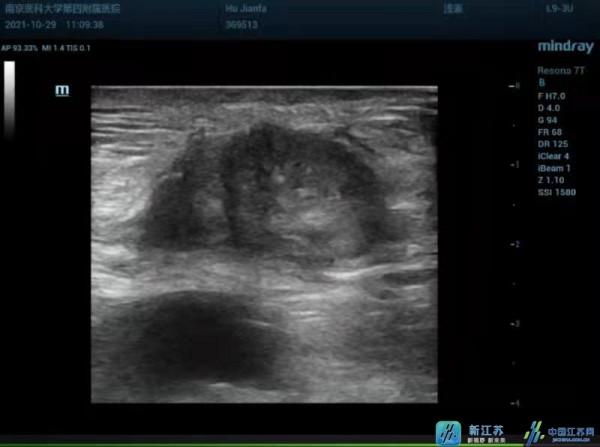

患者男性,52歲,發現腹壁腫塊5月餘入院。患者2020年5月曾行右半結腸癌根治術。2021年3月行腹腔鏡下直腸癌根治術+降結腸造口術,術後多次放化療。2021年5月直腸癌復發並造瘻口周圍轉移,行降結腸造口關閉+部分迴腸切除+迴腸橫結腸吻合+橫結腸造口。入院查體:腹壁見多處陳舊性手術瘢痕,右下腹結腸造瘻口,左中腹切口下方觸及一大小約3cm×2cm包塊,質硬,邊界不清,活動度差,疼痛評分8分,無法入眠。增強CT+增強磁共振均提示:腹前壁皮下軟組織異常強化影,考慮轉移癌。因病灶距造瘻口較近,外科無法切除。經多學科會診後,擬採用超聲引導下微波消融治療。

在普外科和手術室配合下,楊光斌醫師透過超聲造影評估病灶位置、範圍與周圍組織關係;超聲引導下穿刺針進入病灶周邊注入生理鹽水,有效分離病灶與周圍組織;超聲引導下微波針進入病灶中心,以35W×360s間斷固定+移動靶點消融+冰鹽水間斷冰敷,強回聲逐步覆蓋病灶;術後超聲造影病灶無增強。消融過程1小時,術後疼痛評分2分,兩小時後下地,當晚睡眠質量佳。